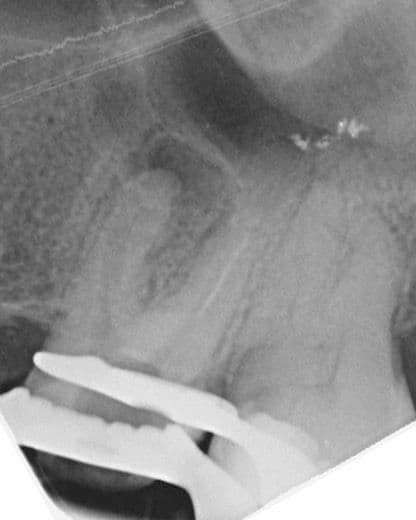

Tedavi esnasında dişin meziobukkal kanalının apikal üçlüsünde alet kırığı meydana geldi. İlgili kırık alet bypass yapılmaya çalışıldı ancak başarılı olunamadı ve kanalda basamak oluştu. Dişin vital olduğu da göz önünde bulundurularak kök kanalları doldurularak dişin takibine karar verildi (Şekil 2).

(Şekil 2) 2023 Mayıs Post-Op radyografi